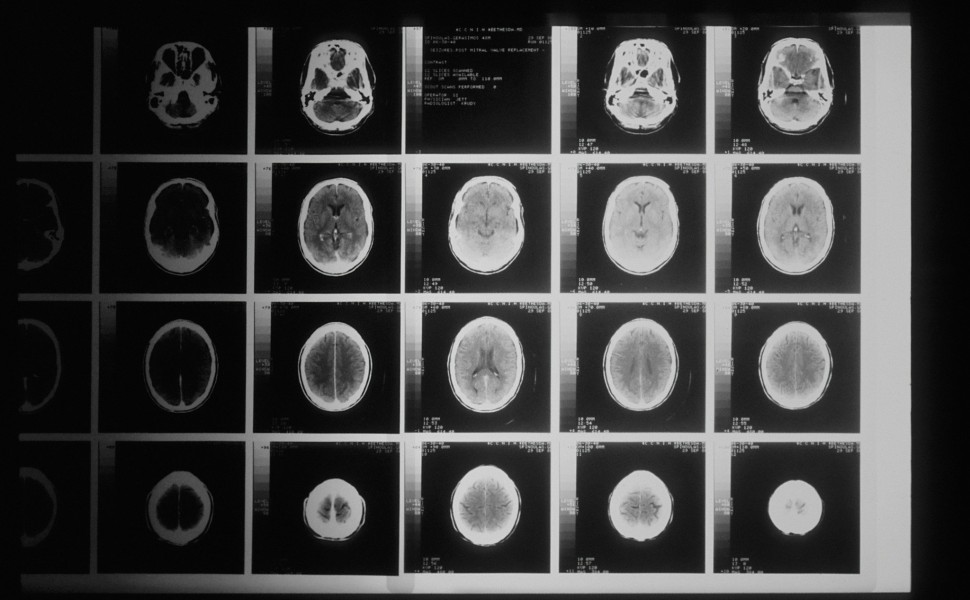

Την τεχνική του Έλληνα γιατρού, που ξεκίνησε τις σπουδές του στη Θεσσαλονίκη, Αναστάσιου Γιαμουριάδη και εφαρμόζει μια τεχνική αφαίρεσης όγκων «στο μέγεθος μήλου» από τον εγκέφαλο μέσα από τα φρύδια, παρουσιάζει το Sky News.

Μέχρι σήμερα για τα περισσότερα περιστατικά όγκων στο μπροστινό μέρος του εγκεφάλου απαιτείται από τους χειρουργούς να αφαιρέσουν ένα μεγάλο τμήμα του κρανίου - αποκαλύπτοντας κατά την κρανιοτομή υγιή τμήματα του εγκεφάλου.

Ο κ. Γιαμουριάδης, ο οποίος εργάζεται για το NHS Grampian, εξήγησε ότι η μέθοδος που έχει αναπτύξει δεν είναι καινούργια αλλά ο ίδιος την έχει τροποποιήσει ώστε να έχει «περισσότερο χώρο, μέσω του φρυδιού για να αφαιρεί πολύ μεγάλους όγκους του εγκεφάλου».

«Μέχρι σήμερα οι ασθενείς έμεναν με ουλές σε όλο τους το μέτωπο, κάτι που αποφεύγουμε με τη μέθοδο αυτή. Για να είχαμε πρόσβαση στο σημείο που ήταν ο όγκος έπρεπε να κάνουμε κρανιοτομή, κάτι που απαιτούσε πολύ μεγάλο χρονικό διάστημα - μόνο για να φτάσουμε στον όγκο χρειάζονταν έως και τρεις ώρες- και συνολικά η προσέγγιση αυτή διαρκούσε 8 έως 10 ώρες» προσθέτει ο κ. Γιαμουριάδης.